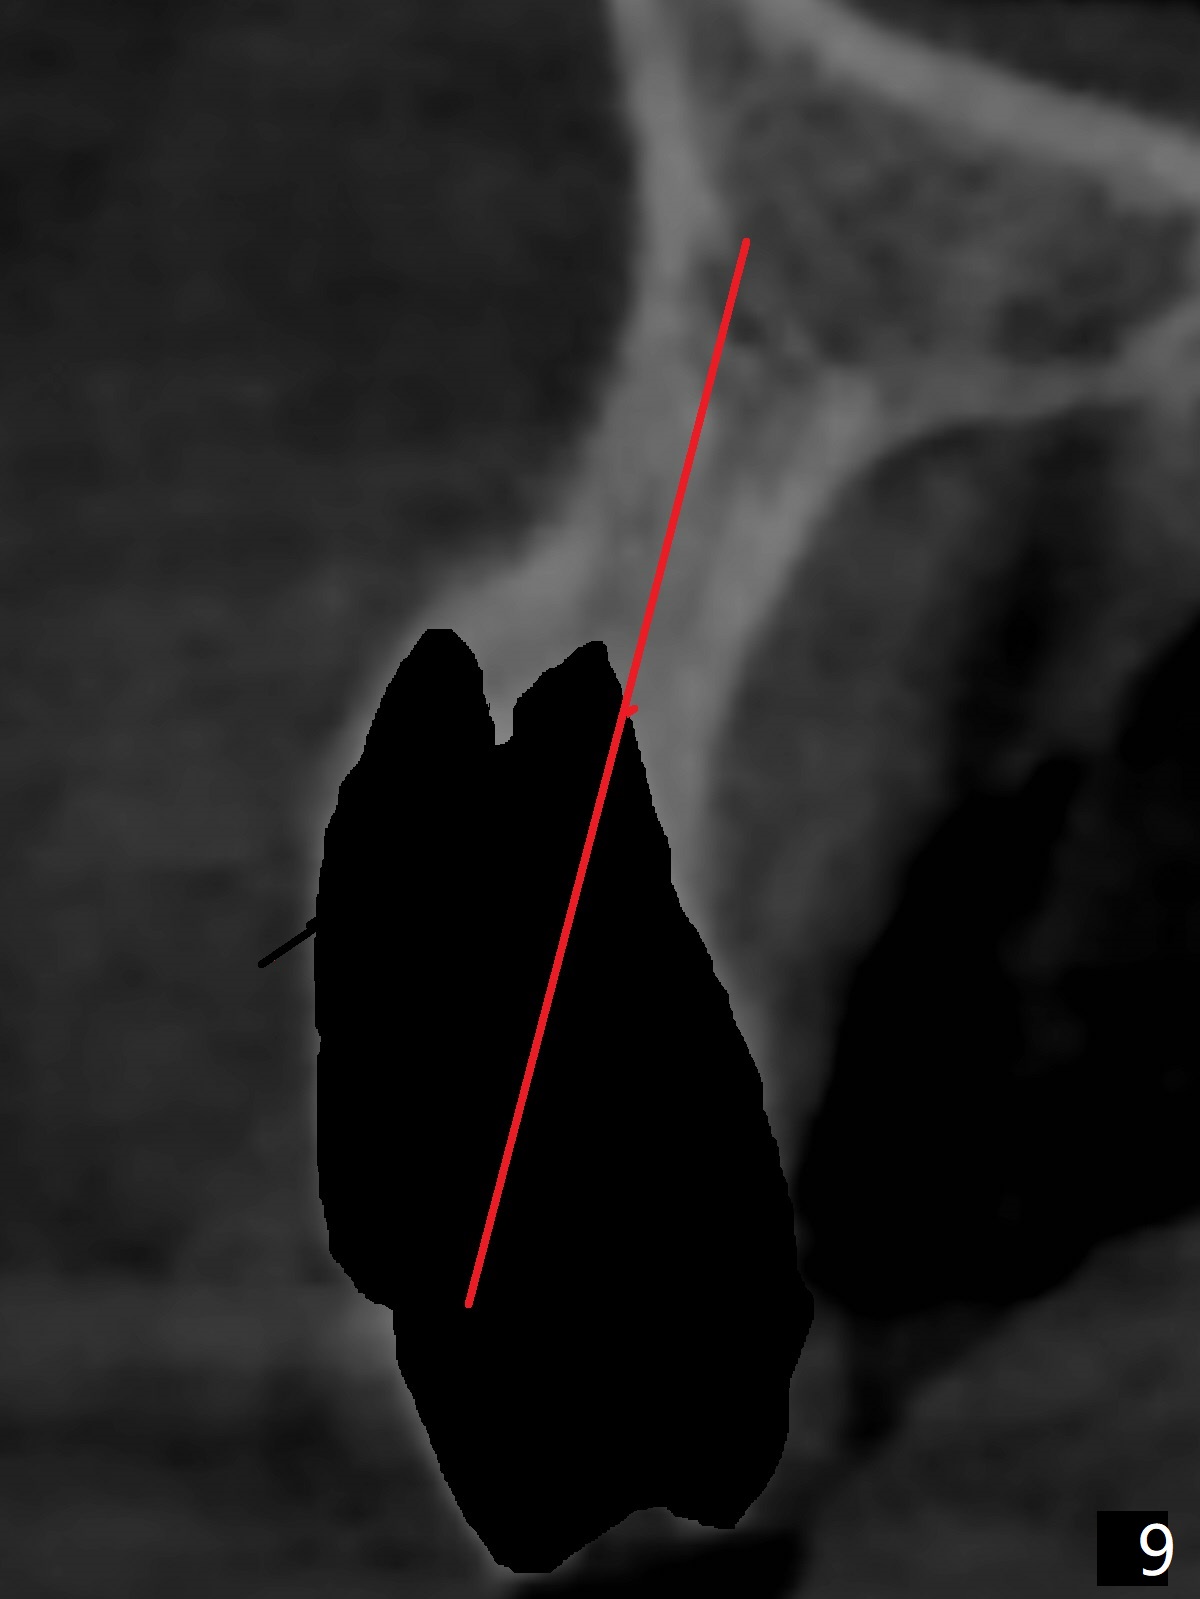

A 51-year-old woman lost the teeth #6 and 7 due to odontoma removal ~30 years ago. The area was restored with a FPD. The latter is removed with immediate implant at #8 8-9 months earlier. Particulate bone graft does not repair the bone deficiency at #6, 7 (Fig.2,3), although the soft tissue looks bulky (Fig.1). It appears that the palatal defect also needs a piece of bone block to fill in (Fig.4). The block will be harvested from the chin (Fig.5,6). If the block graft turns out to be impracticable, the periodontally compromised tooth #5 (bone loss, Fig.2,3,7) will be extracted for immediate implant. Initial osteotomy will be established in the palatal socket (Fig.8,9). Either a 2- (Fig.10) or 1- (Fig.11) piece implant will be placed. After wound healing, impression will be taken for a lab-fabricated provisional FPD.